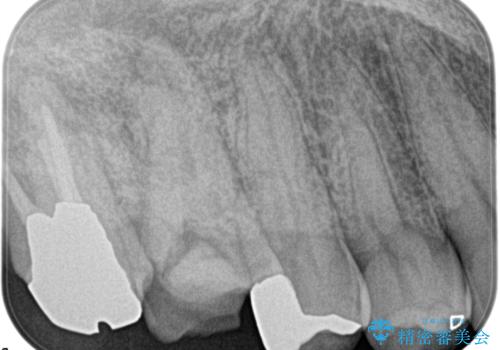

湾曲根管。精密根管治療

検査の結果、右上第一大臼歯の診断を、歯髄壊死とし抜髄を行っております。

湾曲根管に対してエラーなく処置を行えております。